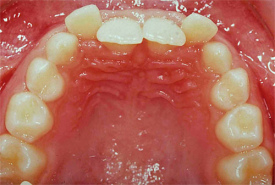

Zahnfehlstellung Engstand

Engstand nennt sich der Platzmangel der Zähne bei

einem zu kleinen Kiefer [6]. Kiefer werden zu klein

-- durch zu wenig Wachstumsreiz, wenn das Kind nicht

gestillt wird, sondern immer die Flasche bekommt [2]

-- durch Verlust der Milchzähne im frühen Kindesalter

durch Flaschenkaries, so dass die Milchzähne ihre

Rolle als "Platzhalter"nicht mehr wahrnehmen können

[5].

Engstand der Zähne, eine Frontalansicht |

Engstand bei einem Unterkiefer, eine Sicht

von oben (mit Sicht auf die Oberflächen,

lat. Facies [7]) |